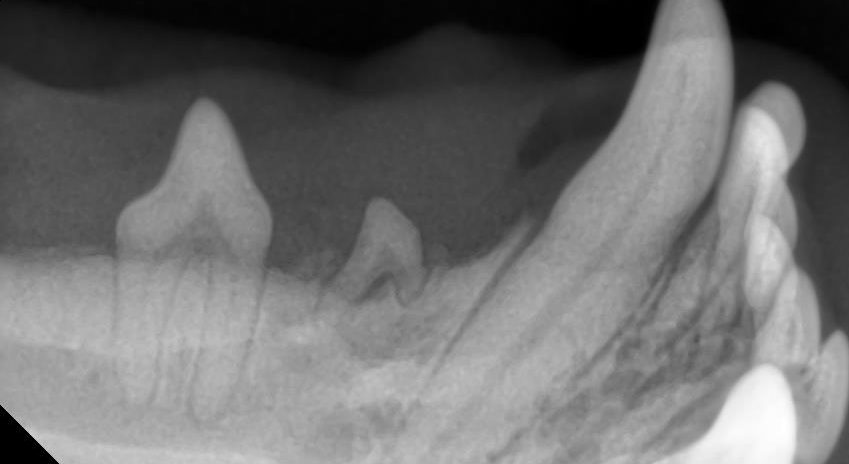

歯科用のレントゲンやCT撮影によって、歯の位置や状態を詳しく確認できます。

右側も同様の歯列異常がありましたが、歯科レントゲンを撮影したところ右下顎第二前臼歯の未萌出と診断しました。